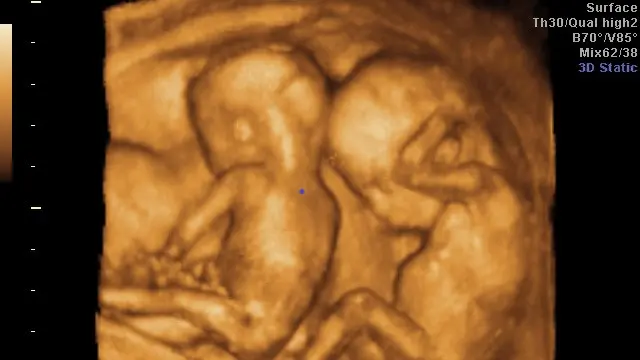

¿Qué se realiza en el ultrasonido de estos embarazos?

• ❤ Evaluación de la corionicidad, es decir si se trata de un embarazo gemelar con una placenta en la que ambos gemelos la comparten o bien dos placentas, una para cada gemelo, ya que de acuerdo a ello será la vigilancia en estos embarazos

• ❤ Si son embarazos gemelares con una sola placenta, la evaluación y el seguimiento deberá ser más estrecho, ya que que hay mayor riesgo de complicaciones en estos embarazos.

• ❤ La ecografía es el mejor método diagnóstico no sólo para identificar una gestación gemelar, sino también para catalogarla y especificar su corionicidad (número de placentas) y su amniocidad (número de bolsas).